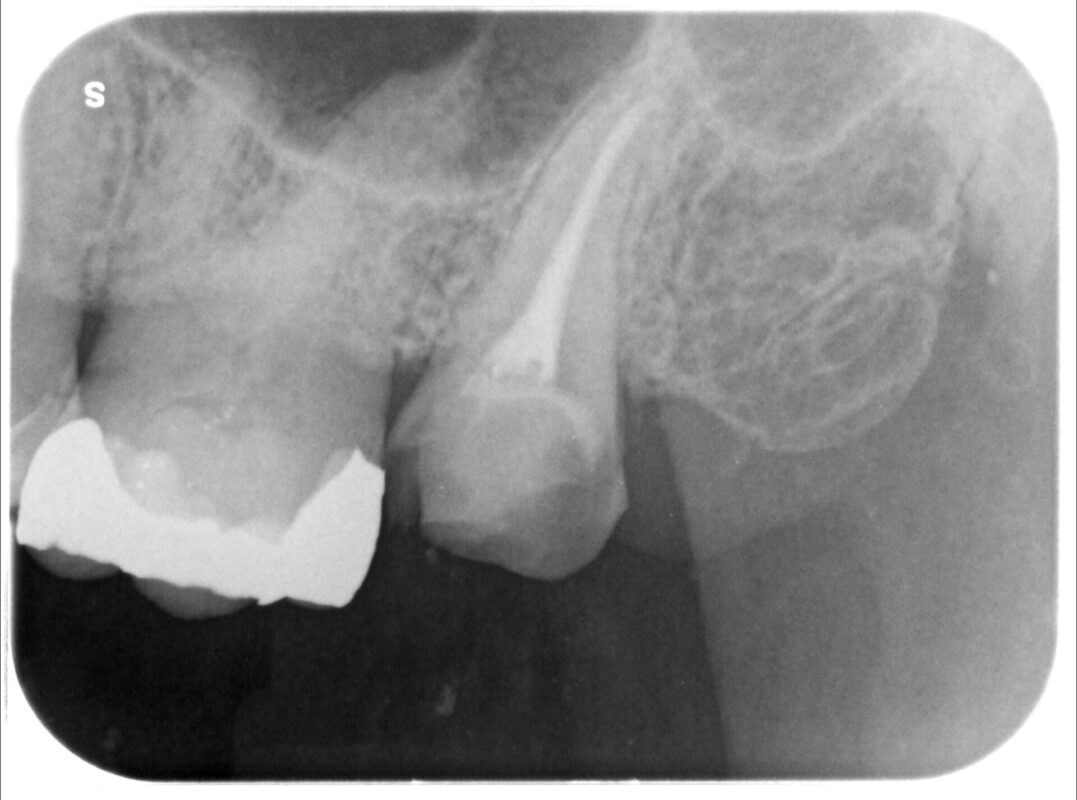

そこで当院において、再婚間治療行い、

術後

虫歯を歯肉外に引っ張り出すためエクストゥルージョン開始。

2週間ほどで3mm出てきました。

この後歯周外科治療を行い、治癒を待って補綴治療行います。